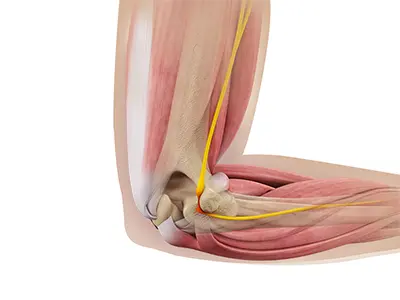

Ulnar Nerve Release

Ulnar nerve release, also known as ulnar nerve decompression, is a surgical procedure to treat a medical condition called ulnar nerve entrapment.

Cubital Tunnel Syndrome

When the elbow is bent, the ulnar nerve can stretch and catch on the bony bump.

Cubital Tunnel Release (Medial Epicondylectomy)

Cubital tunnel release is a surgical procedure to correct cubital tunnel syndrome.